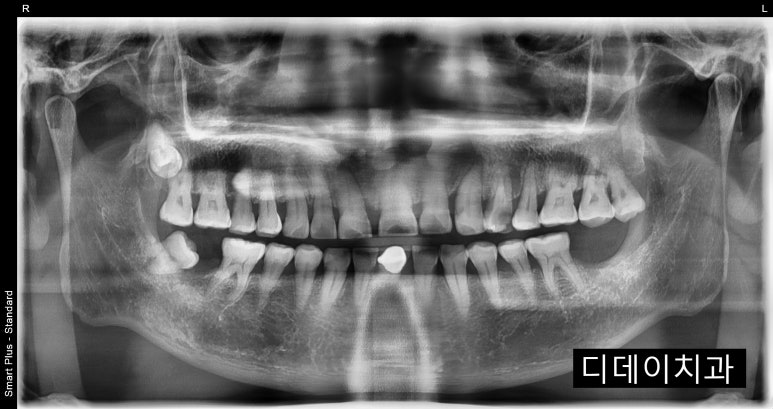

임플란트 수술 전 이미 치아가 발치되어 있는 상태

2023-01-06

치과에 오시는 환자분들 중에는 이미 치아가 발치 되어있는 환자분들도 꽤 계신데요.

다른 치과에서 발치를 하신 경우도 있고, 잇몸 상태가 너무 좋지 않아서 저절로 치아가 빠진 경우도 있습니다.

치주염이 악화되어 잇몸뼈가 소실된 나머지 치아를 계속 지탱하고 있을 수 없어 치아가 빠져버리는 것이죠.

예를 들어 만약 환자분이 오늘, 2024년 1월 18일에 저희 치과에 오셔서 엑스레이를 찍으셨다고 가정해볼게요.

엑스레이에서 임플란트 해야할 치아가 있었던 것이 확인이 되는 경우에는

추후 발치 후 임플란트를 식립한다면 아마 보장받으시는데 큰 문제는 없으실 겁니다.

치아가 상실된 상태에서 내원해주신 케이스

2023-03-03

하지만 만약 임플란트 해야하는 치아가 엑스레이 상에서 확인이 되지 않는다면 문제가 될 수 있어요.

다른 치과에 해당 치아를 발치했다는 기록이 있고, 엑스레이로도 확인이 가능한 경우라면 괜찮지만

자연적으로 빠진 경우에는 보장개시일 이후 치아가 있었다는 것이 증명되지 않으니

임플란트치아보험 지급을 거절할 수도 있습니다.